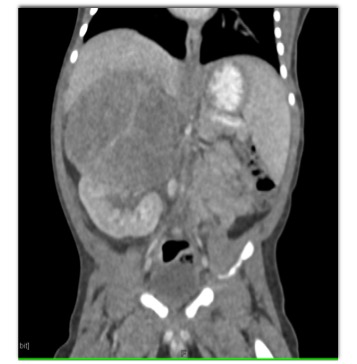

The best diagnosis in this 4 month old is?

Wilms tumor

adrenal hematoma

adrenal carcinoma

Neuroblastoma